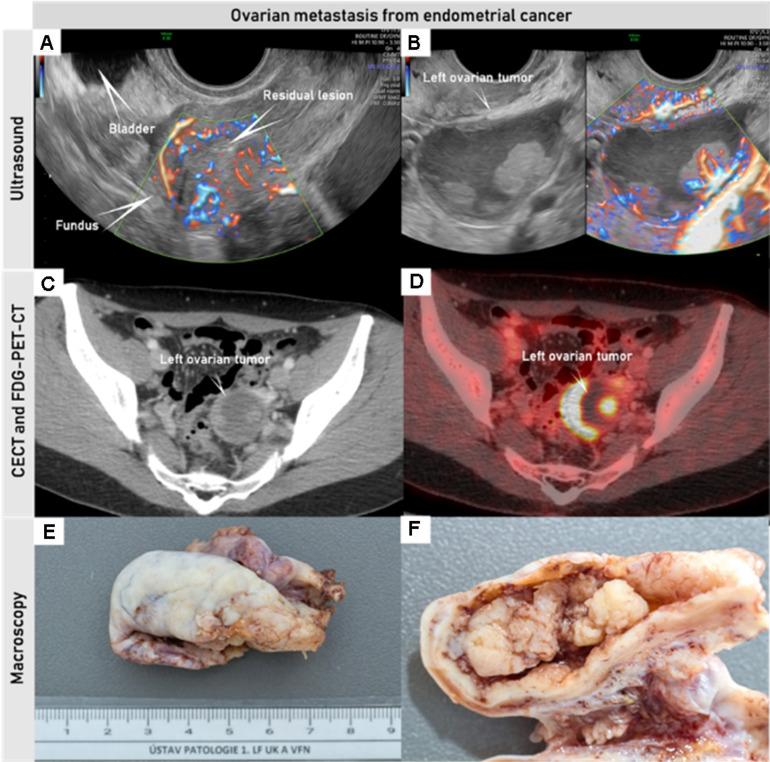

妇科癌症的影像学分期和超声的作用:欧洲联合共识声明的更新。

Staging by imaging in gynecologic cancer and the role of ultrasound: an update of European joint consensus statements.

In recent years the role of diagnostic imaging by pelvic ultrasound in the diagnosis and staging of gynecological cancers has been growing exponentially. Evidence from recent prospective multicenter studies has demonstrated high accuracy for pre-operative locoregional ultrasound staging in gynecological cancers. Therefore, in many leading gynecologic oncology units, ultrasound is implemented next to pelvic MRI as the first-line imaging modality for gynecological cancer. The work herein is a consensus statement on the role of pre-operative imaging by ultrasound and other imaging modalities in gynecological cancer, following European Society guidelines.

摘要

近年来,盆腔超声诊断成像在妇科癌症的诊断和分期中的作用呈指数级增长。来自最近的前瞻性多中心研究的证据表明,术前局部超声分期在妇科癌症中具有很高的准确性。因此,在许多领先的妇科肿瘤学单位,超声与盆腔 MRI 一起被用作妇科癌症的一线成像方式。本文是根据欧洲社会指南,就超声和其他成像方式在妇科癌症中的术前成像作用达成的共识声明。